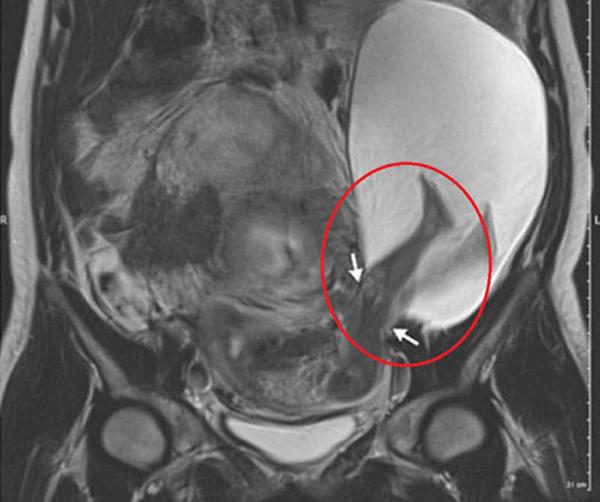

Sức mạnh cú đá của các bé sẽ được xác định bằng cách kiểm tra mô hình xương chân bào thai thông qua chụp MRI ở các giai đoạn khác nhau trong thai kỳ.

Kết quả cho thấy, một thai nhi khỏe mạnh thì cú đá có sức nặng trung bình khoảng 4,76kg (tương đương 47N). Đặc biệt, bé càng lớn thì cú đá sẽ nhẹ bớt đi.

Cụ thể, khi 20 tuần, sức nặng cú đá khoảng 2,95kg nhưng đến 38 tuần thì con số này giảm xuống chỉ còn 1,72kg. Các nhà nghiên cứu cho rằng lý do là vì bé càng lớn thì càng có ít không gian để di chuyển trong bụng mẹ.